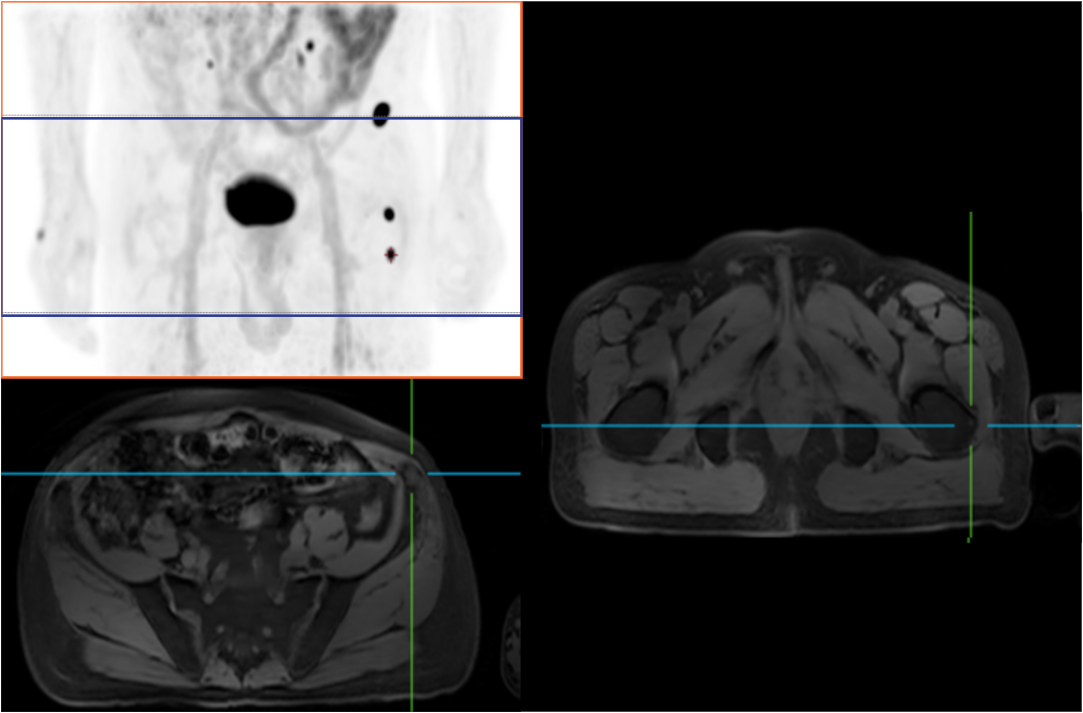

PET/MRは分子機能と構造画像を完全に結合し、腫瘍、心血管疾患、神経疾患、小児疾患、炎症性疾患の臨床診断に欠かせない手段として役立っています。

AFOVが、従来の20cm~25cmのPET装置と比較して、32cmの長尺AFOVであることにより、感度が向上するだけでなく、全身の主要臓器や転移が考えられる局所リンパ系において1ベッドポジションでがんのTNステージを実現することが可能となります。

従来、腫瘍系のPET/MR撮影には約35~50分かかっていました。長いAFOVは、PET/MRの腫瘍スキャン方式をさらに最適化することができます。局所PET/MRスキャン後に腫瘍の局所リンパ転移の有無に基づいて全身をスキャンするかどうかの判断を最適化でき、転移のない患者さまのスキャン時間を短縮できる可能性があります。

2019年8月、Peking Cancer Hospitalはユナイテッド イメージング ヘルスケアのPET/MRを導入し、長いAFOV下でのがんTNM病期決定の徹底的な探求と最適化を行いました。500例以上の様々な臓器のスキャンにより、長い AFOV PET/MRは1つのベッドポジションでのスキャン範囲を大幅に拡大し、がんTNMステージングの効率を向上させることができることが証明されました。

乳がん、食道がん、前立腺がんなどのTNMステージングを「時空間統合」ULTRA-clear TOF PET/MRの長軸視野で最適化した事例を紹介します。